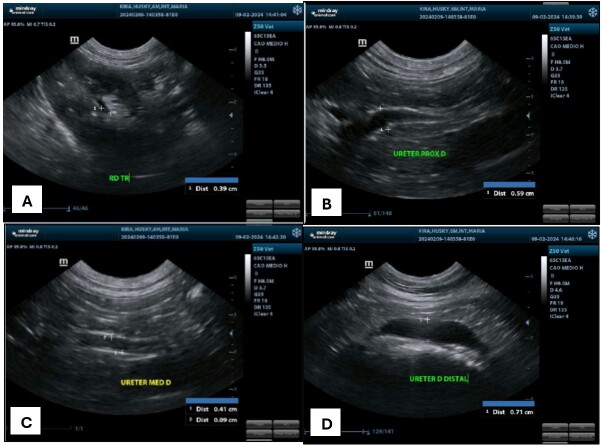

Ureteral ectopia is a congenital malformation characterized by the abnormal location of the distal aspect of one or both ureters, being classified according to its anatomical path as intramural or extramural. The most common clinical sign is urinary incontinence. The presence of other associated urogenital anomalies, such as hydroureter, hydronephrosis and ureterocele are possible, being the last one a rare condition characterized as a cystic dilation of the submucosal layer of the distal ureter. The diagnosis is based on patient history, clinical signs and imaging exams. Treatment consists in surgical correction, with the technique variating according to the condition classification, and the prognosis is favorable, however most animals remain incontinent. This paper objective to report the diagnostic and clinical surgical conduction of intramural unilateral ectopic ureter correction associated to ectopic ureterocele in a Siberian Husky, 7-months-old, attended at Veterinary Hospital of Federal Rural University of Rio de Janeiro with complaint of urinary incontinence and clinical history of bacterial cystitis. The diagnosis of intramural unilateral ectopia associated with ureterocele was obtained through abdominal ultrasound and excretory urography, being confirmed with surgery. The surgical technique performed was neoureterostomy, and there were no trans or post-surgical intercurrence. Despite maintenance of the ureterocele and right ureter and renal pelvis dilation two days after surgery, observed during abdominal ultrasound, these alterations has positive evolution one week after the surgical procedure. Patient presented significant improvement of urinary incontinence two months after surgery.